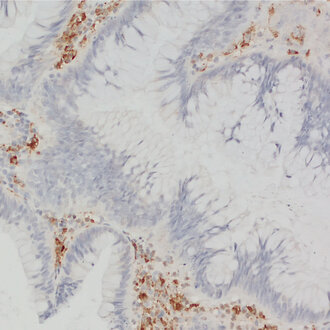

CD68 staining detects macrophages in human colon adenoma

CD68, also called Lamp-4 in humans or macrosialin in mice, is a highly glycosylated type I transmembrane protein that belongs to the lysosome associated membrane protein (LAMP) family (1). CD68 expression is increased in cells associated with elevated phagocytic and degradative activity. High CD68 expression is detected in cells of the mononuclear phagocyte lineage including macrophages, osteoclasts, and myeloid dendritic cells (2). CD68 is a marker of activated microglia and only expressed at low levels in resting microglia (3). Staining for CD68 is predominantly intracellular, only 10 -15% of it is found on the cell surface. In oncology research, CD68 is the major biomarker for quantification of tumor-associated macrophages (TAMs) (4). High infiltration of CD68+ macrophages is an independent prognostic factor for overall survival in several tumor entities (5).